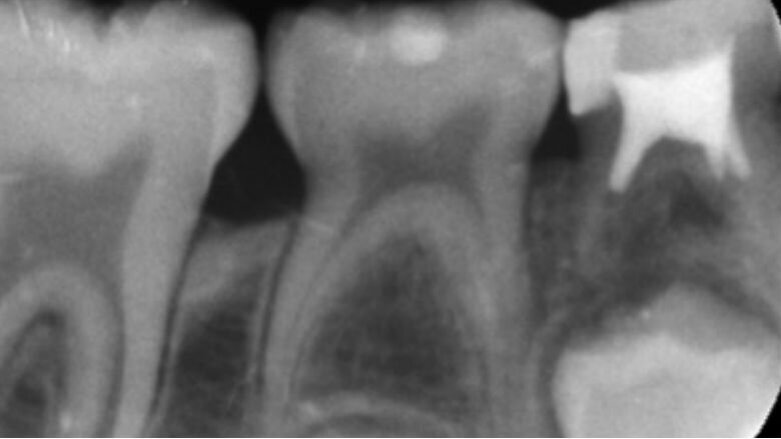

Il tipo di contatto, inoltre, che si stabilisce tra un dente e quello adiacente non è identificabile in un punto, come avviene tra i denti permanenti, ma è rappresentato da una superficie. L’anatomia pulpare si presenta ampia rispetto alle dimensioni coronali, con cornetti pulpari più pronunciati. Tutte queste variabilità anatomiche rendono gli elementi decidui facilmente esposti a trattamenti endodontici, in seguito a processi cariosi.

Il trattamento endodontico del dente deciduo comporta principalmente due procedure: la pulpotomia e la pulpectomia. Non è consigliabile eseguire degli incappucciamenti della polpa poiché dalla letteratura si evince che la percentuale di successo a lungo termine è minore rispetto a quelle che si ottengono nei trattamenti di pulpotomia. La pulpotomia è il trattamento endodontico più utilizzato negli elementi decidui che mostrano l’interessamento della sola polpa camerale in seguito all’esposizione accidentale di una porzione di essa dovuta a un processo carioso o a un trauma, purché il dente risulti asintomatico per i segni clinici di sofferenza pulpare e non presenti segni radiografici di lesioni periapicali.

La pulpectomia è un trattamento che prevede la rimozione dell’intero organo pulpare, sia coronale che radicolare. È indicata nei casi in cui la polpa è vitale ma irreversibilmente infiammata o non vitale a causa di lesioni cariose avanzate o di traumi. Il fine del trattamento endodontico è quello di controllare l’infezione e quindi eliminare i batteri patogeni del sistema canalare.

Tale trattamento è influenzato da vari fattori legati principalmente all’anatomia radicolare, alla sottigliezza del pavimento della camera pulpare, all’impossibilità di stabilire l’esatta collocazione del forame apicale, sia clinicamente che radiograficamente, effetto dovuto al rimaneggiamento che avviene durante il processo di rizalisi. A oggi la misurazione elettronica della lunghezza di lavoro appare il metodo più affidabile per evitare una sovra strumentazione.